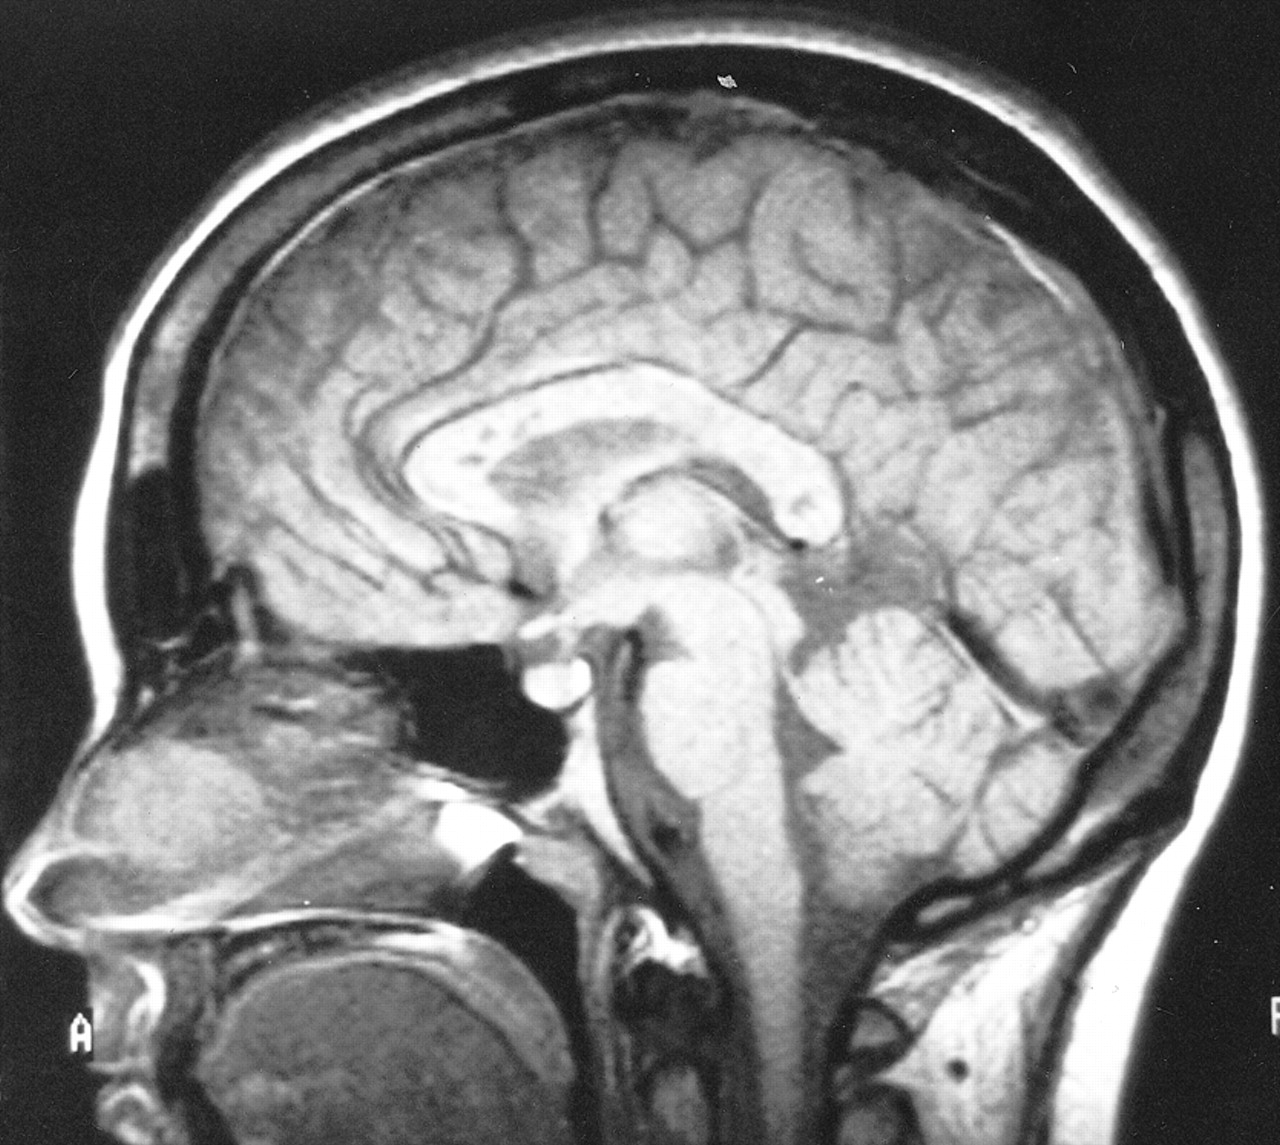

多病灶的幕上的白质病变,包括胼胝体(图1),在所有27个病人,有频繁的参与小脑,中间小脑总花梗,和脑干图1,表)。病变众多,往往是小(3 - 7毫米)但有些小病变成为支流和一些大的(> 7毫米)。19病人实质增强,当明显,导致大脑的粟粒状的外观(图2)。胼胝体的损伤通常是小的,并且涉及中央与周边的相对保留纤维;增强是变量。急性胼胝体的病变(图3)中观察到的活动脑病取而代之的是一个“充满”/穿孔先生出现在后续所有27例(图4),可能代表microinfarctions,没有出现在其他地方。胼胝体,最好在薄片(3毫米厚)矢状T1或T2矢状/质子密度加权图像,由一系列小(3毫米)中央孔相隔7毫米矢状T1和T2矢状/质子密度图像。这些扩展在整个长度的胼胝体。当急性(“雪球”)(见大图3)胼胝体的病变,慢性残余孔较大,尤其是在压部。线性缺陷有时看到的,可能反映microinfarction间接辐射在胼胝体轴突。中央孔(见图4)被认为是由于横向辐射的胼胝体轴突的微型心肌梗塞的可能性。

有深的灰色基底节和丘脑病变19病人(参见表),通常体现在T2信号强度增加,质子密度,和天赋的图像。大病变类似“巨大陷窝”43并建议纹状体外动脉增的广泛参与。三个这样的病人显示这些病变显著增强,伴随着leptomeningeal增强。实质增强(见图2)有关的大脑区域,偶尔与leptomeningeal增强(见相关表)。串行扫描被执行,增强可能是更常见。脑病减弱和病人开始恢复,只有残余病灶中央(见胼胝体的洞图4)和一些白质病变。在两个病人,增加信号强度变化在胼胝体伴随着中央胼胝体的洞在最初的MRI检查。更严重影响病人、脑和小脑萎缩随之而来。在两个这样的实例,胼胝体越来越萎缩,前面提到的胼胝体的洞几乎消失了。